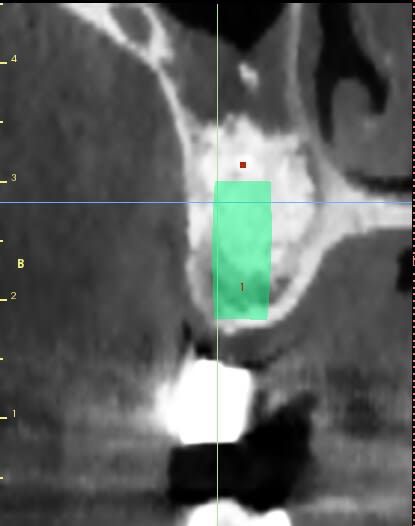

patiente ayant été implantée il y a 12 jours et toujours mal

le sinus lift a été pratiqué il y a 8 mois

les implants ont été posés sans problème, et le BM était bien dense

ce qui m'ennuie ce sont les douleurs 12 jours après l'implantation

Aspect lacunaire du biomat au scanner = sucre mouillé infecté...car non vivant et non vascularisé

bon je m'en doutais un peu que ça venait des lacunes dans le bio oss